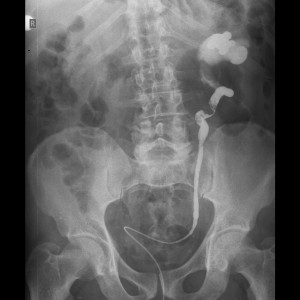

Να σημειωθεί ότι βραβεύτηκε ως η καλλίτερη ελεύθερη ανακοίνωση η εργασία με τίτλο: «Διαγνωστική προσπέλαση σε ουροθηλιακό καρκίνο του ουρητήρα με MR πυελογραφία», με συγγραφείς τους Ελ. Αποστολίδη, Θ. Ζιάγκο, Χ. Πασπαλάρη, Ν. Χατζηλεωνίδα και Ι. Ποντίκη.